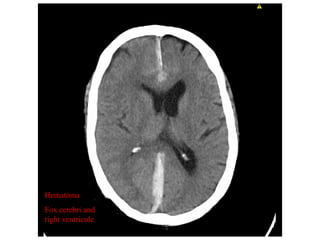

The document discusses a case of a 61-year-old man with small cell lung carcinoma who sustained a fall while hospitalized, resulting in a subdural hematoma. It analyzes contributing factors such as psychotropic drugs, low platelets, and muscle atrophy, proposing improvements like better communication among healthcare staff and supervision during patient mobilization. Recommendations emphasize the need for careful monitoring and support for at-risk patients when they begin to walk again.